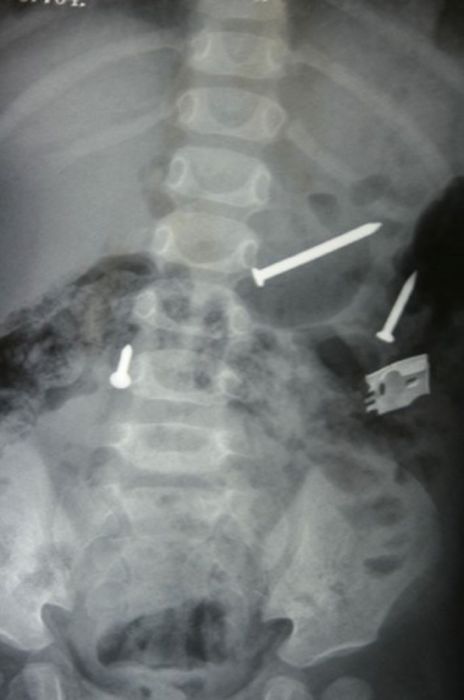

Рентгеновские снимки людей, которые умудрились сами или с чужой помощью разместить внутри своего организма разные посторонние предметы. От вилок и ножей до пуль и бензопилы (!!!). По этическим соображениям обычные снимки таких травм и повреждений выкладывать нельзя, зато рентгеновские можно – на них травмы видны достаточно условно, хоть и очень понятно.